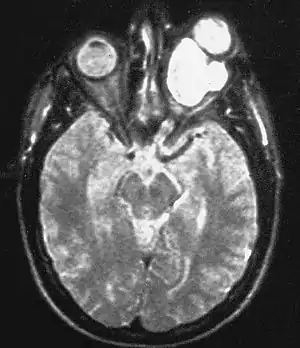

Magnetic resonance image of a large retrobulbar optic nerve tumor causing massive proptosis

Optic nerve gliomas are diagnosed using magnetic resonance imaging (MRI) and computed tomography (CT) scans.[5] The tumor adopts a fusiform appearance, appearing wider in the middle and tapered at the ends.[5] Enlargement of the optic nerve along with a downward kink in the mid-orbit is usually observed.[5] While CT scans allow for optic nerve evaluation, MRI allows for intracranial evaluation to observe if the tumor has extended to other regions such as the optic chiasm & hypothalamus.[6]